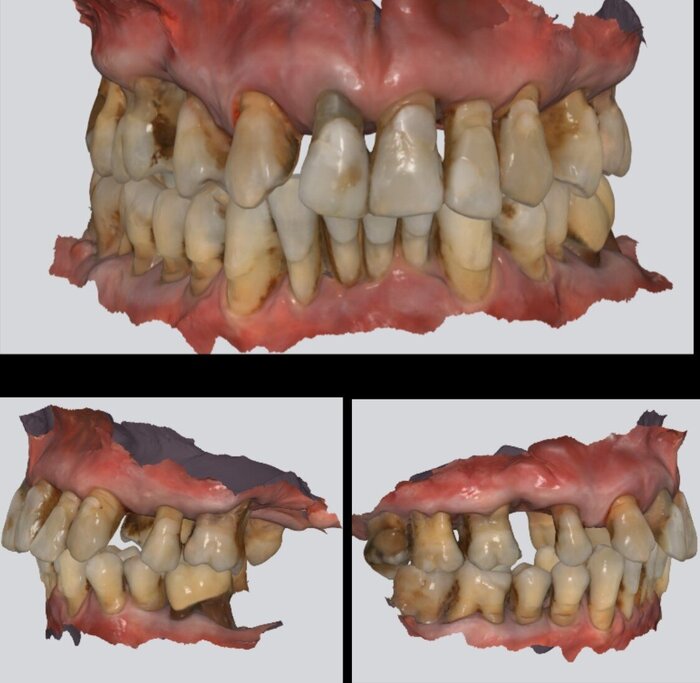

Из главы 14, вы тоже уже знаете, что когда мы удаляем зуб, то кость в той области начинает атрофироваться, так как организм-существо рациональное и не видит смысла кормить ткани, которые не работают. Сага о стоматологии. Глава 14. Заживление после удаления зуба

Практически во всех областях рта атрофия идет снаружи, соответственно, добавлять кость будем снаружи, а в области задних отделов верхней челюсти атрофия идет ещё и со стороны гайморовой пазухи, так как на её стенки давит воздух. Всё это умножается на мягкую кость, которая у нас традиционно располагается в этой области, и время пока пациент у нас не соизволит заняться своими зубами, и получаем истончение, в результате чего имплантат туда установить невозможно без наращивания.